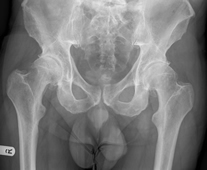

X-ray showing severe bilateral hip osteoarthritis. Enlarge